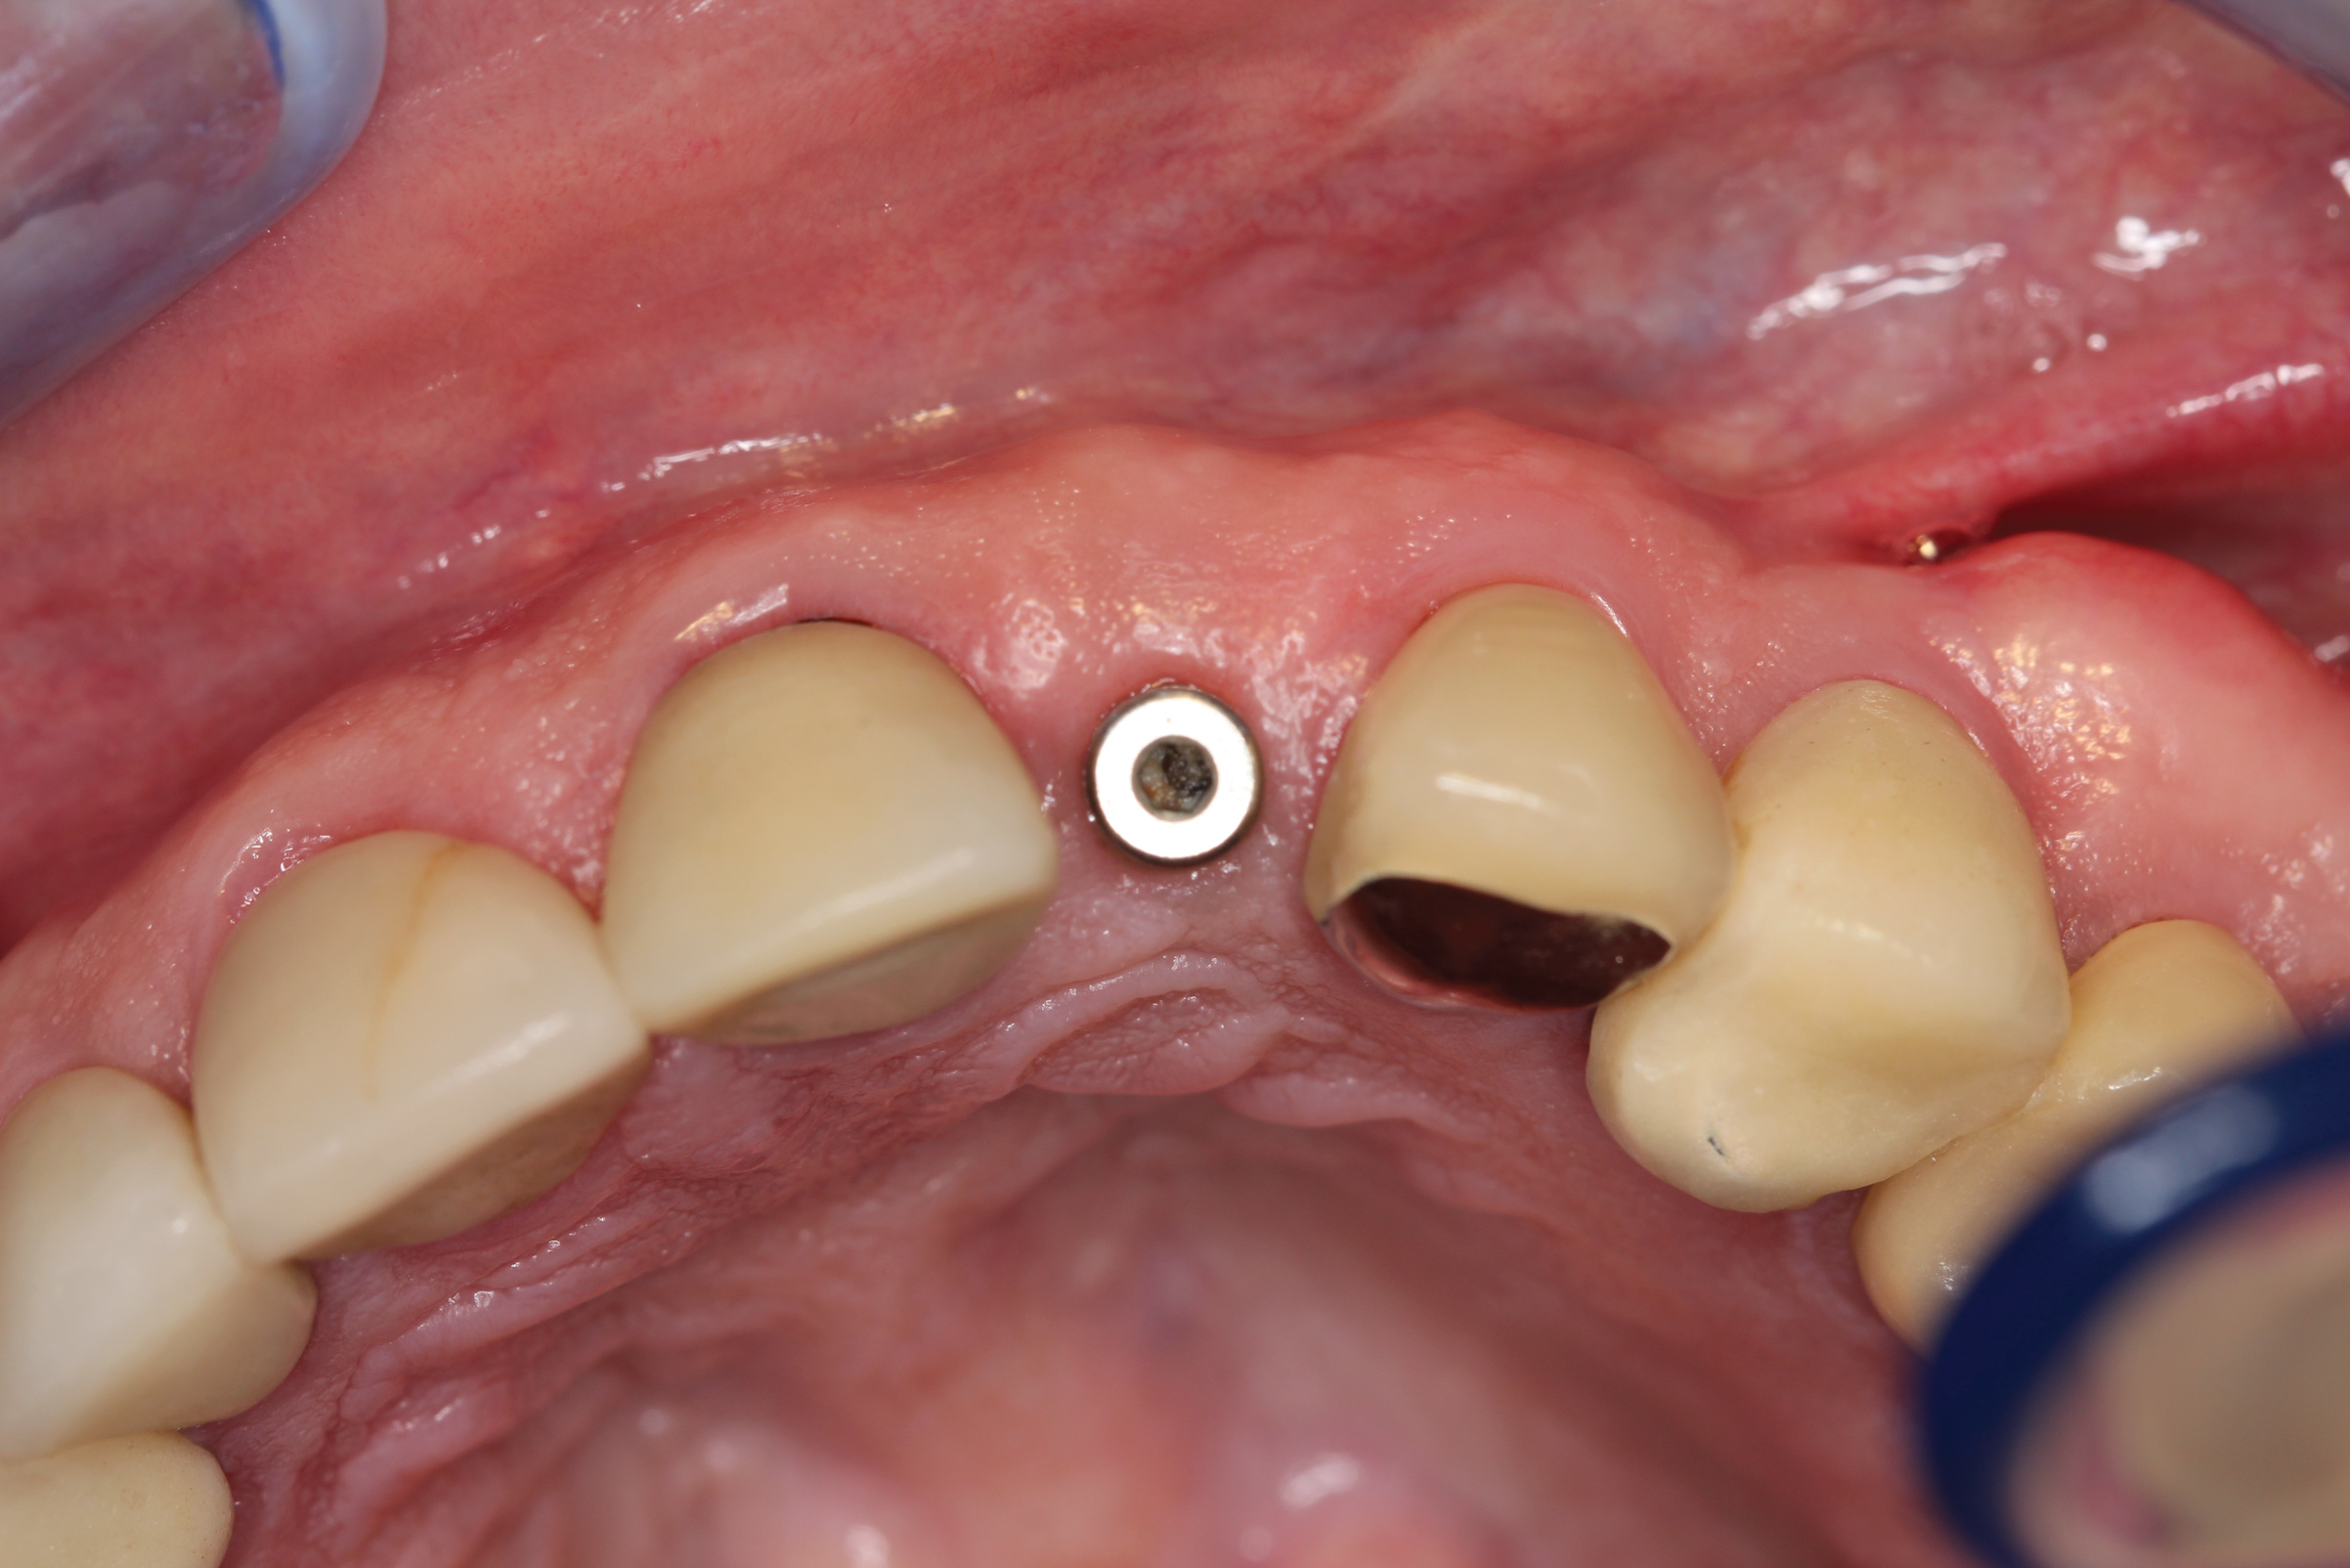

After 2 weeks, excellent soft-tissue healing and maintenance of the labial gingival tissue was evident. The same was true after 3 months (Figure 21). The gingival zenith continued to be maintained after 1.5 years (Figure 22). Importantly, the facial wall bone thickness of the implant also was maintained at the 1.5-year follow-up (Figure 23), suggesting favorable maintenance of this case.

Fig 21. Soft-tissue healing after 3 months. Note maintenance of the facial gingival zenith.

Figure 21

Fig 22. Final restoration after 1.5 years. Note the soft-tissue contour on the buccal aspect.

Figure 22